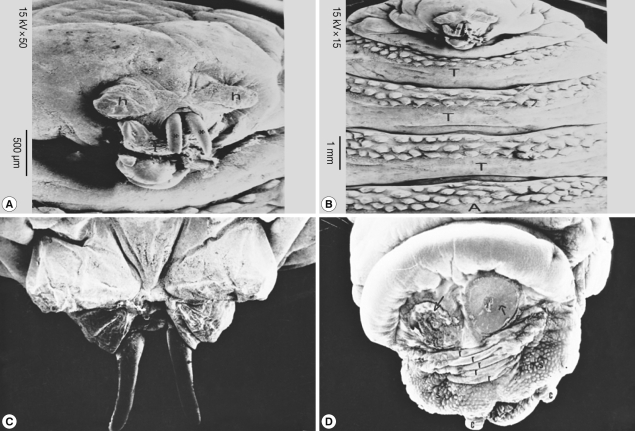

SEM findings

Scanning of the second stage larvae of Sarcophaga species showed that mouth hooks were smooth in outline. The mouth vestibule was pear-shaped. The sides of the cheek had lateral striations that were directed laterally and upwards (Fig. 4A, B). The anterior spiracles have 10 finger-like openings (Fig. 4C). The posterior spiracles were located in a deep cavity and each contains 2 elongated spiracular opening. At the posterior end, 6 pairs of papillae were observed, 2 pairs dorsal, 2 ventral, and 1 on each side of the posterior end (Fig. 4D).

Scanning of the third stage larvae of Sarcophaga species (Fig. 5) showed that the anterior end had a wide and strongly spined vestibular opening through which a longitudinally striped structure, ending in a curved sharp hook, protruded on each side (Fig. 5A). The dorsolateral aspect of each of these structures was provided with 2 anterior and 2 posterior processes (Fig. 5B). The anterior spiracles extended laterally from the second segment (Fig. 5C). Each of the 12 finger-like processes ended with more or less circular spiracle openings. The posterior end was surrounded by more pronounced spines (Fig. 5D). It was provided with 2 anal cerci and 8-10 pedunculated papillae. The posterior spiracles were not visualized since they were located in a very deep pit.

SEM of the third stage larvae of Oestrus species is shown in Fig. 6. The top view of the ventral surface of the larvae showed that the first segment (head) beared 2 ventrally curved hooks with pointed ends (Fig. 6A). The oral hooks extruded from the mouth orifice lying between a tongue-like process ventrally and 2 horn-like structures dorsally. The head was followed by 3 thoracic rings, with 3 regular rows of single-ended and caudally projected spines (Fig. 6B). The dorsal view of the anterior part of the larvae showed 2 protruded oral hooks and the extremity characterized by its butterfly shape (Fig. 6C). The posterior spiracles appeared strongly sclerotized surrounding the outlet of the respiratory canal completely, followed by 5 anal rides and 2 caudal swelling (Fig. 6D).